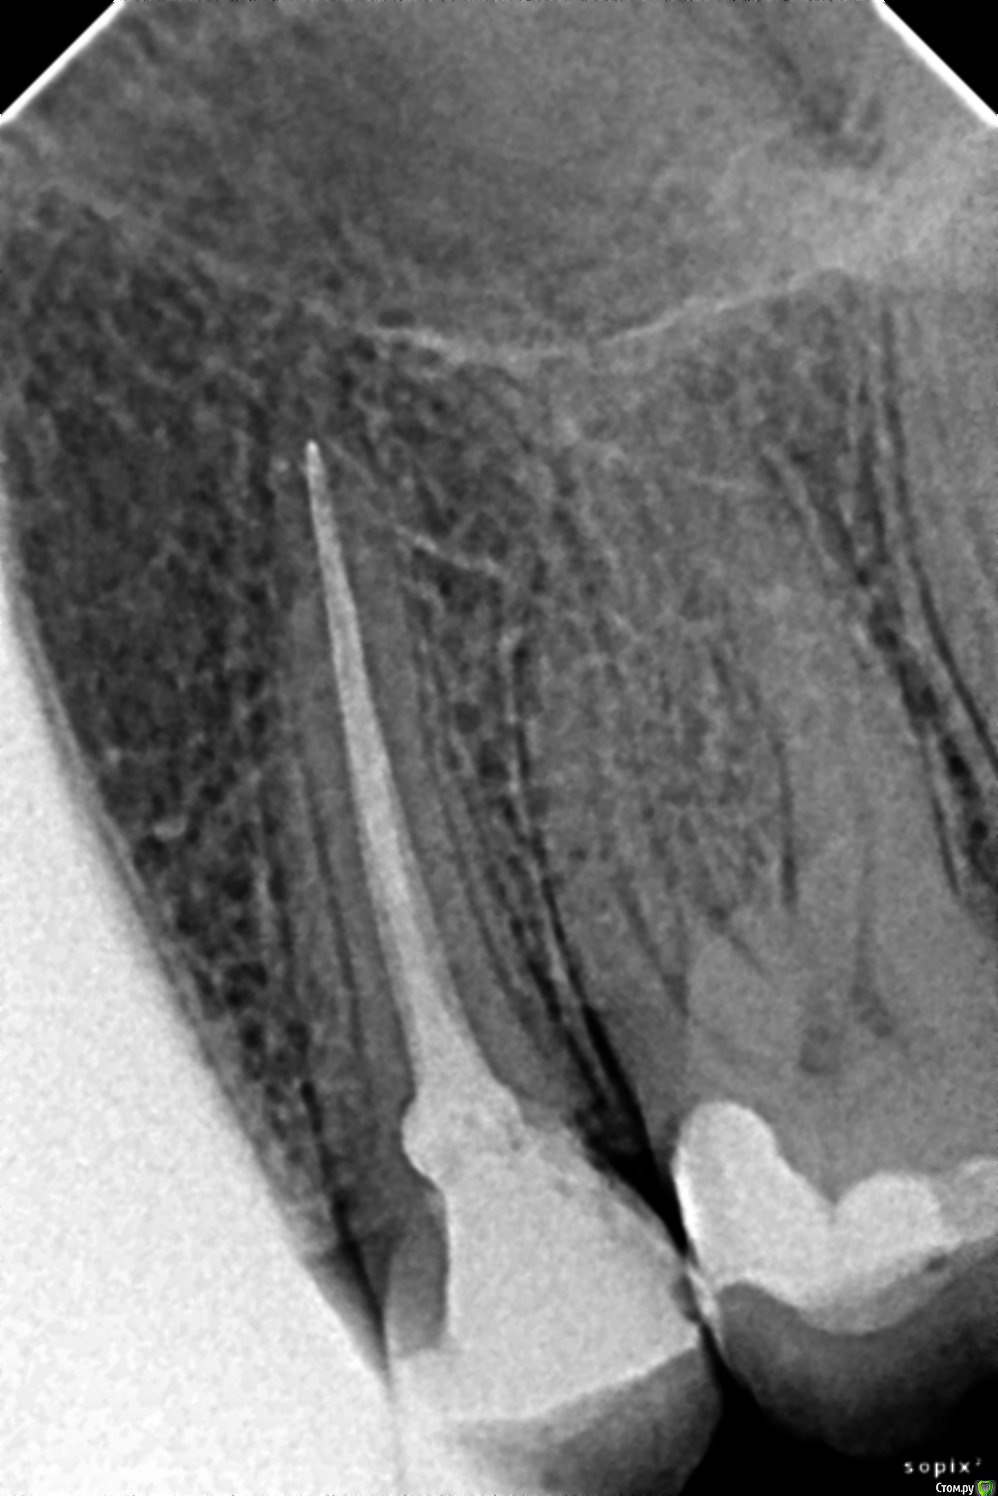

Verasss Опубликовано 11 сентября, 2016 Поделиться Опубликовано 11 сентября, 2016 Здравствуйте! Посоветуйте, пожалуйста! Имеется 25-й зуб, запломбированный месяц назад горячей гуттаперчей, инъекционный метод вертикальная конденсация. Постоянная боль уже месяц после пломбировки, чувство внутреннего отека, одонтогенный гайморит (по кт и симптомам) как следствие. До пломбировки не беспокоил. Единственное, что переходила с каласептом - 17 дней. Зуб депульпировали сразу, поставили каласепт на неделю, я проходила с ним 17 дней. Потом запломбировали 08.08 горячей гуттаперчей, вертикальная конденсация. Постпломбировочные боли в течение недели.Через неделю осталась ноющая боль и ощущения отека где-то внутри в десне. с 08.08 по 22.08 принимала обезболивающие (кетанов+найз), так как спать и разговаривать было больно.22.08 несмотря на мои жалобы на ноющую боль, мне сняли временную и поставили постоянную пломбу. Два дня боли не было, потом она возобновилась, отдавала в передние зубы, в ноздрю, куда-то в бровь. Больно было разговаривать. Обезболивающие днём и на ночь.29.08 боль ушла, необходимость пить обезболивающие отпала. Cохранился отёк, ощущение, чтобы зубы или прикус не встали на место, щелкает челюсть слева, при надавливании на зуб он чувствителен, зуб убран из прикуса по максимуму. 05.09. Боль вернулась. Если зуб или десну рядом потревожить начинается ноющая боль, которая сама по себе не прекращается. Болит как бы не сам зуб, а ткани под ним и окружающие его. 07.09 сделала кт, по которому вся гайморова пазуха со стороны зуба заполнена. Вторая чистая. с 08.09 начала принимать антибиотики. Сейчас есть признаки гайморита, немеет ноздря, отек губы (прошел, немного отек щеки), иногда отдает в лоб, голову, передние зубы, но нос чистый без насморка. Перкуссия зуба по-прежнему очень чувствительна, такни вокруг ноют и есть ощущение их мягкости. Вопрос: вскрывать зуб и лечить кальцием или "само пройдёт" на антибиотиках??Параллельное лечение у ЛОРа рекомендовано, само собой. Хотя гноя, как я понимаю у меня пока нет. Прилагаю снимок "до" и "после" (с временной пломбой от 15.08). Есть ещё КТ, могу загрузить папку со всеми фото, программа для просмотра у меня не открывается. Спасибо за содействие! Ссылка на комментарий

dok1 Опубликовано 12 сентября, 2016 Поделиться Опубликовано 12 сентября, 2016 Канал перебрать бы. Не до верхушки пломбирован слегка. Ссылка на комментарий

Verasss Опубликовано 12 сентября, 2016 Автор Поделиться Опубликовано 12 сентября, 2016 Канал перебрать бы. Не до верхушки пломбирован слегка.Спасибо! Мне показывали снимки в другой проекции, там канал как бы загибается к концу и сказали, что в этой проекции снимка этого не видно. Жаль, КТ у меня не открывается. Ссылка на комментарий

Ker Опубликовано 15 сентября, 2016 Поделиться Опубликовано 15 сентября, 2016 (изменено) Да простят меня терапевты, мне не нравится ваш зуб... разрушение ниже уровня десны, контактный пункт не создан..Дистально уступ получился, похоже что матрицу недотянули до края зуба, плюс еще стоит посмотреть насчет второго канала. Недопломбировка есть однозначно, хоть и небольшая, канал открывается прямо на рентген апексе. Само не пройдёт. Изменено 15 сентября, 2016 пользователем Ker Ссылка на комментарий